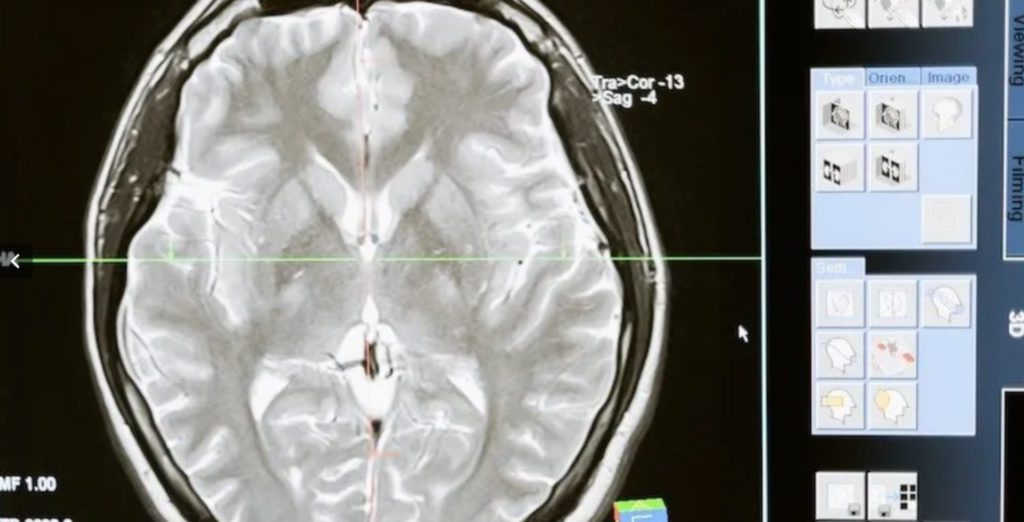

The Director of Global Health Neurology Lab and Founding Director of NSW Brain Clot Bank, the first of its kind in the world, Dr Sonu Bhaskar, spoke to The Australia Today about his ground breaking research.

Dr Bhaskar, who is a physician-scientist and academic neurologist, is well known for his research on prevention and treatment of strokes and leads national and international initiatives on reducing health disparities with a focus on vulnerable populations and under-resourced settings.

Dr Bhaskar told The Australia Today’s Editor, Pallavi Jain that he was always fascinated by the brain and that there are many aspects of the human brain that we still don’t know about.